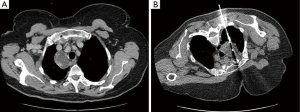

Neck ultrasound revealed an incidental thyroid nodule, but no obvious parathyroid lesion. A technetium sestamibi (99 mTc MIBI) scan showed no evidence of a parathyroid adenoma. Computed tomography (CT) revealed a complex cystic solid mass (Figure 1A) in the mediastinum, closely related to the right lateral aspect of the trachea, the esophagus, the superior vena cava (SVC) and the right subclavian artery and veins.

Figure 1 (A) Computed tomography (CT) scan of the thorax showing a complex cystic solid mass in the middle/superior mediastinum. CT revealed a complex cystic solid mass in the middle/superior mediastinum with peripheral calcification, a solid enhancing component, internal septation and fluid density, seen at the right lateral aspect of the trachea and the esophagus and closely related to the right subclavian artery. These findings were not typical of ectopic parathyroid tissue. There was no significant neck, hilar, axillary or mediastinal lymphadenopathy; (B) CT guided biopsy. A CT guided biopsy was performed following multidisciplinary discussion. It confirmed a 47 mm × 38 mm low attenuation lesion.

A CT-guided biopsy (Figure 1B) was performed following multidisciplinary discussion, confirming a parathyroid adenoma on histology. The patient developed a right sided apical pneumothorax following the biopsy which was managed with a chest drain, and she was discharged. She was readmitted after one week, with a 3-day history of progressive shortness of breath but was hemodynamically stable. A repeat CT scan showed a large right pleural effusion (Figure 2) with no active contrast extravasation.